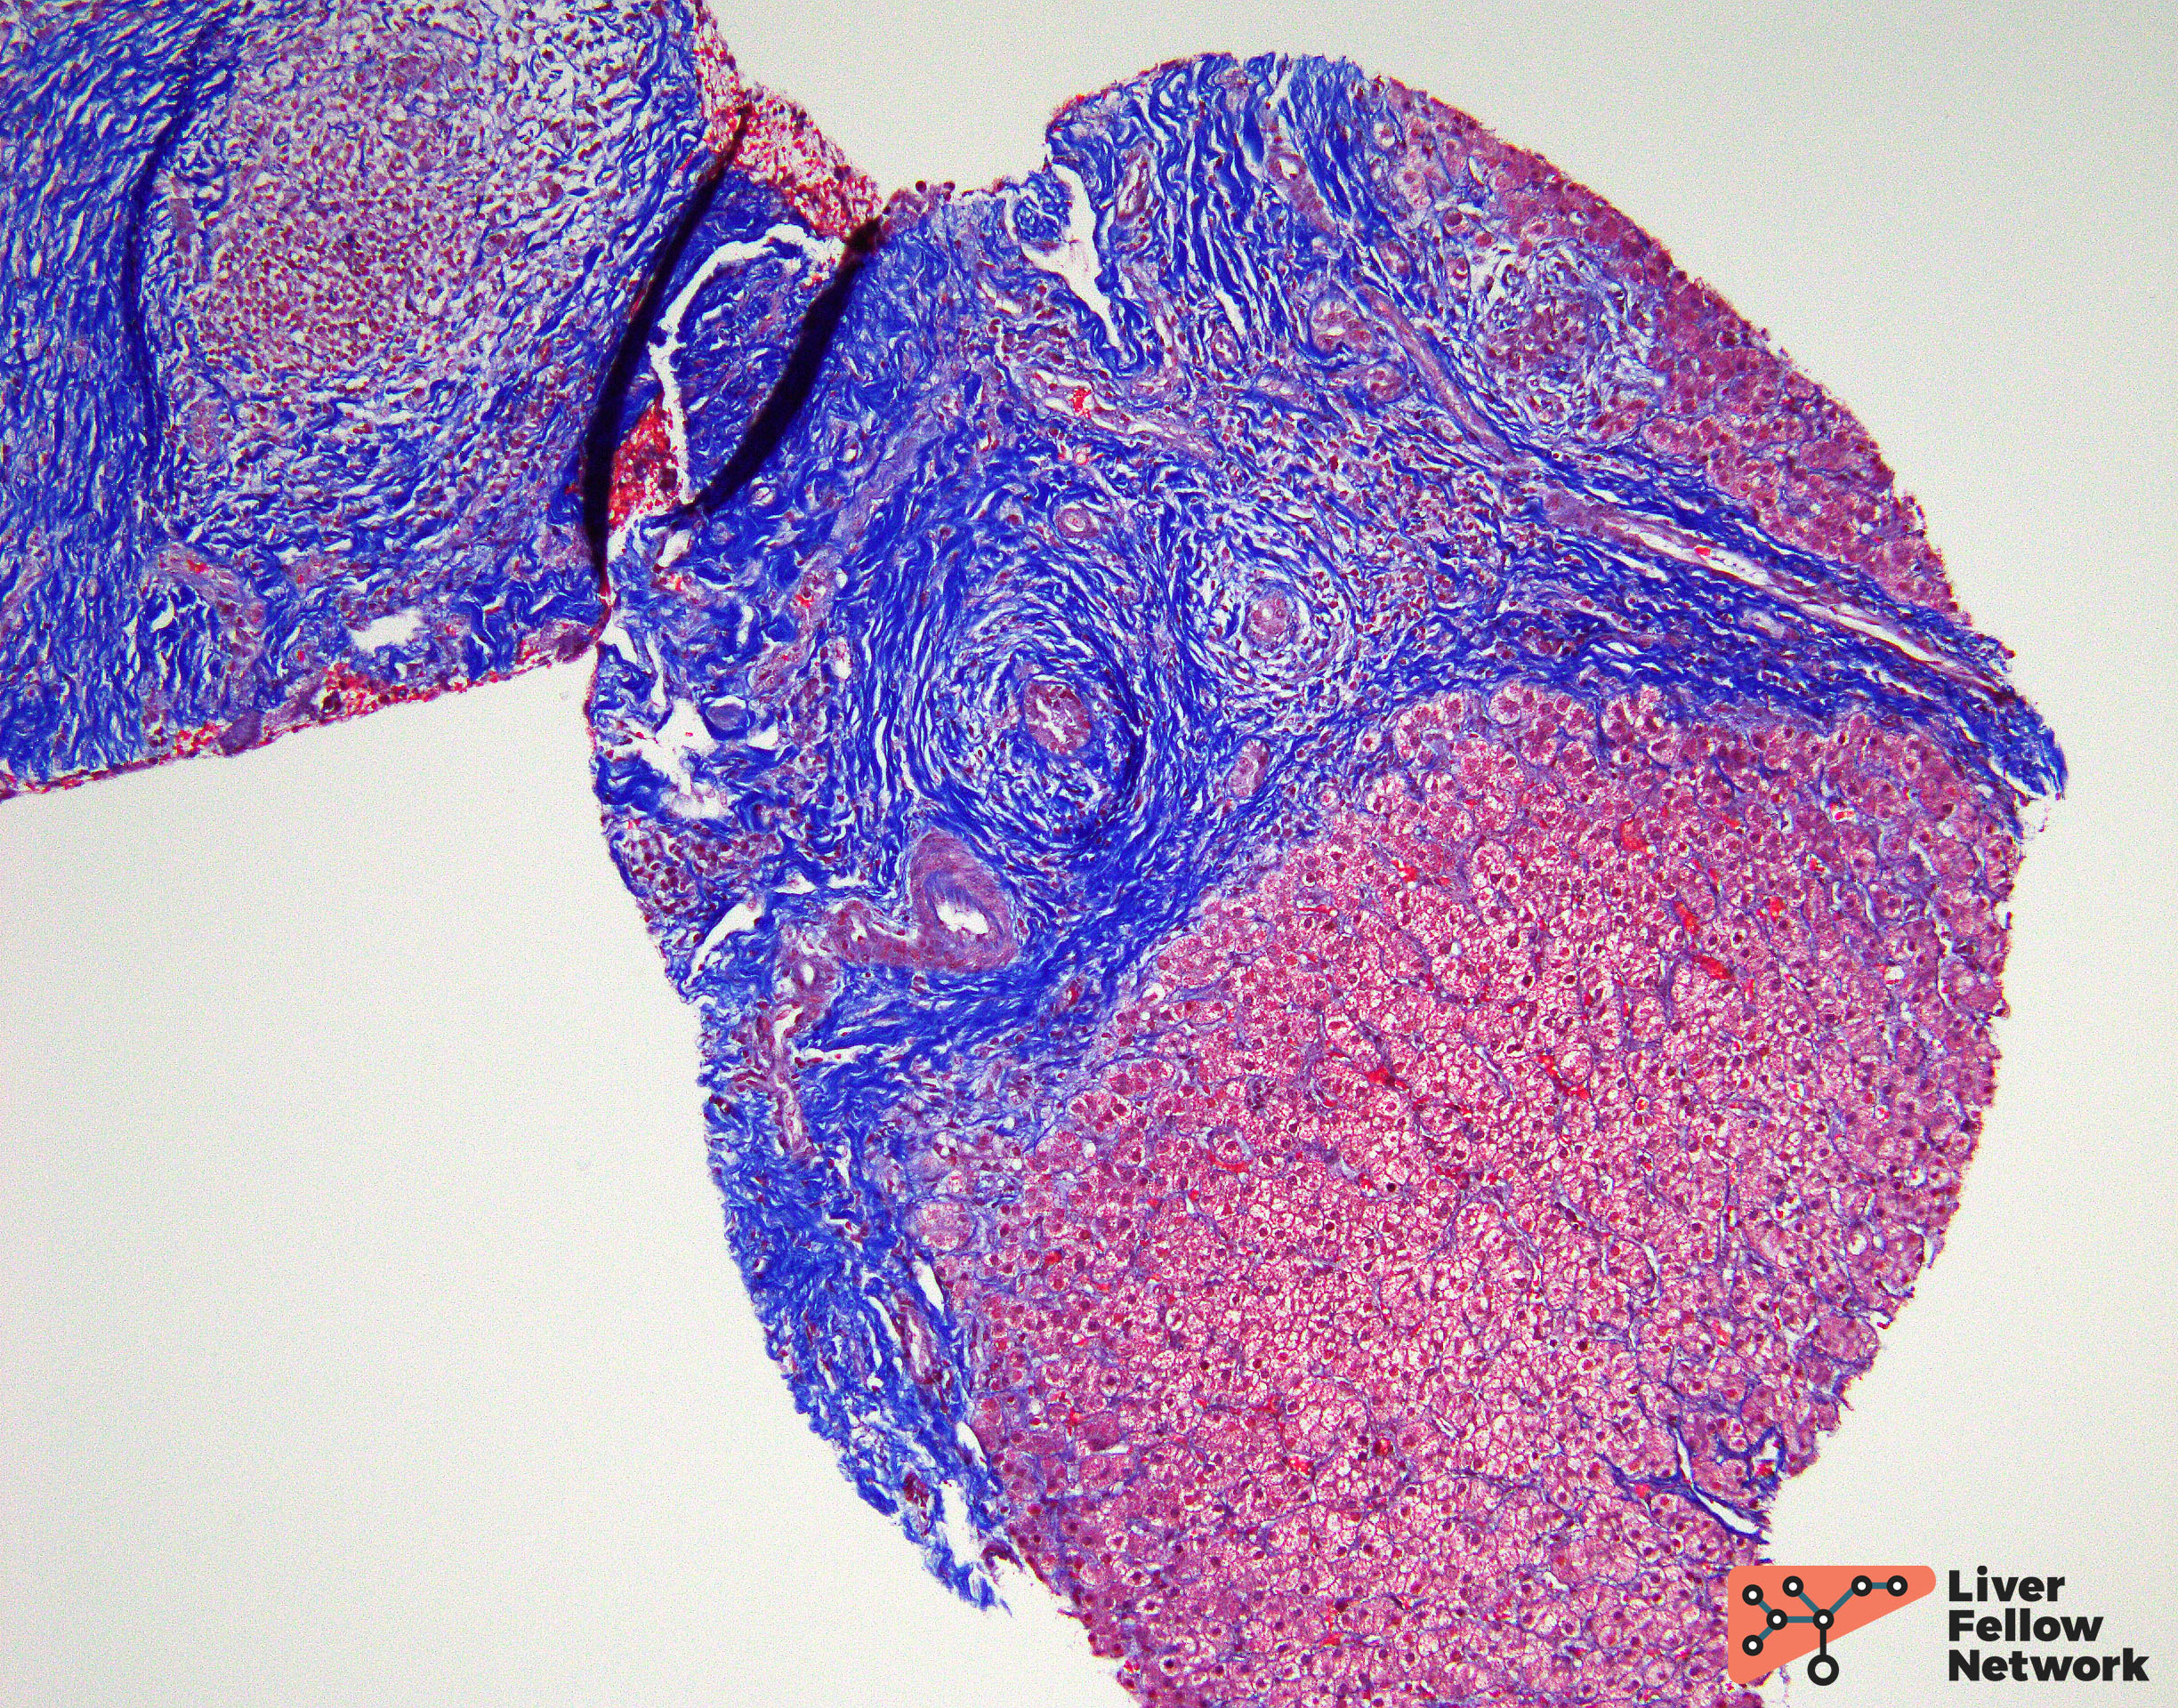

A trichrome  stain highlights increased portal fibrosis (Figure 6).

Figure 6. Trichrome stain demonstrating increased portal fibrosis.

When affected large bile ducts are not sampled, findings in liver  biopsies from patients with PSC may be nonspecific and can demonstrate portal tracts with increased inflammation and fibrosis. There is usually mild lymphocytic portal inflammation with occasional eosinophils. Neutrophils and plasma cells may also be seen. Bile duct injury may be  present; however, the severity depends upon disease duration. Examples of bile duct injury include cytoplasmic vacuolization, epithelial attenuation, and nuclear disarray. Increased intraepithelial lymphocytes may also be identified. Further, secondary changes due to bile duct obstruction may be seen including cholate stasis (Figure 9), bile ductular proliferation, and periportal copper deposition. Over time, chronic injury may result in biliary type cirrhosis – typically described as a “jigsaw puzzle” pattern. There is no to minimal lobular activity.